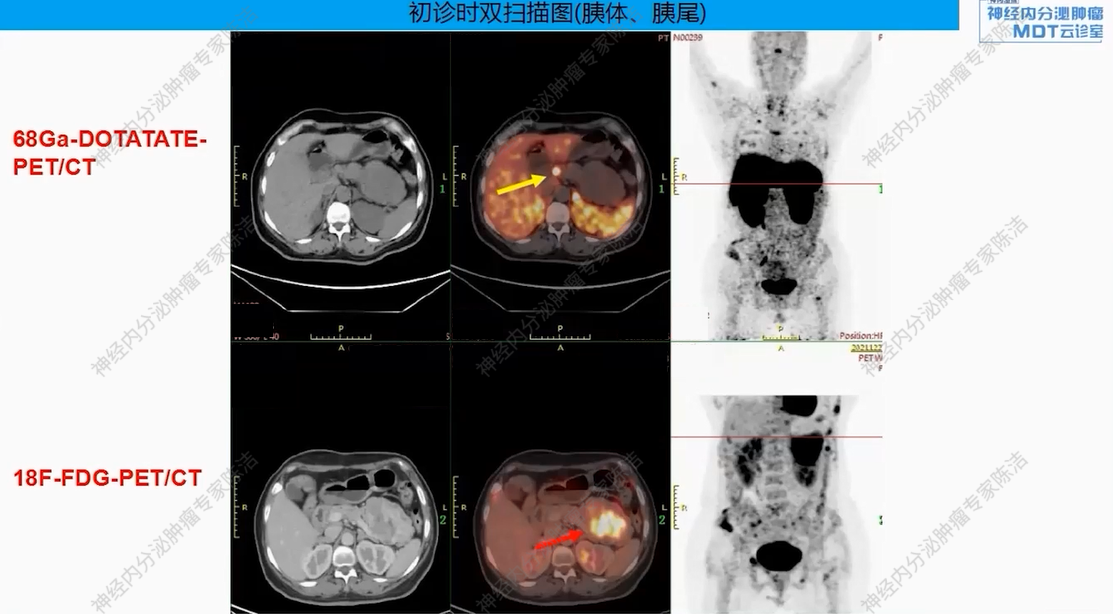

18F-FDG-PET-CT提示:胰尾部见巨大肿物(约8.6*7.2*7.8 cm),FDG代谢明显增高。胰体部另见一小结节(约0.8*0.7 cm),FDG代谢轻度增高。全身多发骨质改变,FDG代谢增高。

68Ga-DOTANOC-PET-CT提示:胰尾部巨大肿块,DOTANOC摄取阴性;胰体部小结节,DOTANOC摄取阳性。甲状旁腺区多发结节,DOTANOC摄取阳性;垂体区稍增大,DOTANOC摄取阳性。

核医学科徐俊彦教授:本病例双扫描PET显像体现了该患者多发肿瘤间异质性。胰尾大病灶(胰岛素瘤)呈SSTR阴性、FDG阳性,这符合约50%胰岛素瘤不表达SSTR的特征。而胰体小病灶呈SSTR阳性、FDG轻度增高。垂体区在SSTR(有生理性摄取)和FDG(无生理性摄取)上均呈阳性,提示垂体瘤可能。骨骼病灶呈SSTR和FDG“双阳性”,高度提示为SSTR阳性的NET转移,但建议对于骨病灶,可对相对表浅的病灶行骨穿以进一步明确骨病灶情况。从最初影像可见髂骨存在明显骨质破坏,甚至骨皮质整体受损,因此骨转移的可能性较大。然而,鉴于该患者同时患有甲状旁腺瘤,甲状旁腺瘤常伴发棕色瘤改变,故目前不能排除甲状旁腺继发的骨改变的可能。

该患者以低血糖为首发症状,影像学发现胰腺占位、甲状旁腺及垂体病变,并检测到MEN1胚系基因大片段缺失而最终确诊。胰腺上同时存在SSTR阴性的胰岛素瘤和SSTR阳性的神经内分泌肿瘤,且骨转移灶(SSTR阳性)极可能来源于后者(胰体小病灶),而非引起主要症状的前者(胰尾大病灶)。